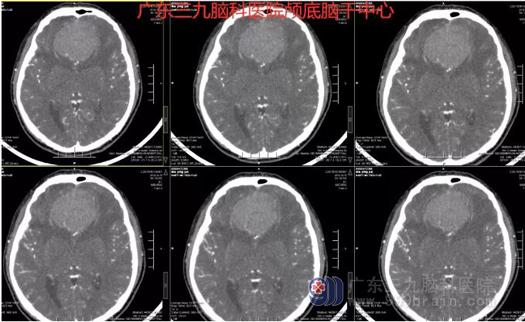

患者马先生今年46岁,20天前无明显诱因下出现视物模糊,当地医院检查头颅CT示前中颅窝占位病变,转院至广东三九脑科医院,神经外一科主任张良给马先生做了详细的检查,视力检查双侧视力仅眼前2米数指,头部磁共振结果显示鞍结节脑膜瘤的可能性大,大小约为56×54×43mm,如果不切除肿瘤,肿瘤会越长越大,甚至有生命危险。

在与患者及家属充分沟通,张良主任带领团队为患者实施了“鞍结节脑膜瘤切除术”,术程顺利,病理报告示: (鞍结节)脑膜皮型脑膜瘤(WHO1级),术后视力左眼4.8、右眼4.9。术后影像复查,他的脑内肿瘤已经完全清除。

图1:术前CTA示双侧额部跨大脑镰(前颅窝底)巨大占位性病变内示多发小血管影。周围示多条血管受推挤改变,双侧大脑前动脉受压推挤向上偏移。

图2:术前MR示双侧额部跨大脑镰(前颅窝底)示一类圆形占位性病变,大小约为56×54×43mm,边界尚清,T1WI呈低信号,T2WI呈等信号,FLAIR序列呈等、稍高信号,周围示轻度长T1长T2水肿影,见环形长T1长T2脑脊液信号环绕,增强后病灶明显均匀强化,邻近脑膜示脑膜尾征,邻近脑组织受挤压。双侧侧脑室前角受压,余脑室系统未见扩张。

图3:术前术后MR示前颅窝底占位性病变切除术后改变,原病灶已切除。